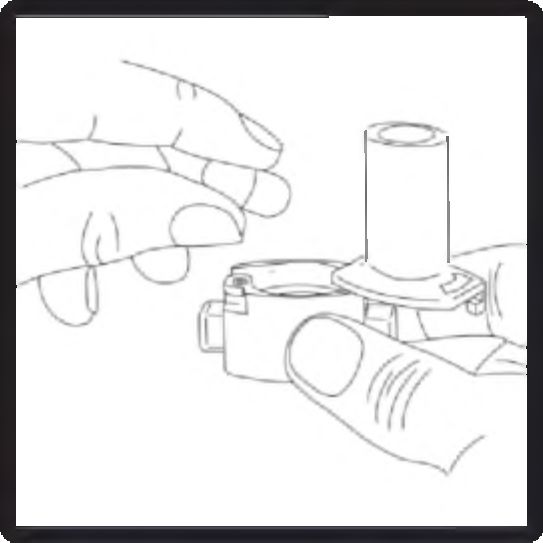

3. Parmaklarınızın tamamen kuru olduğundan emin olunuz. Blisterden bir kapsül çıkarınız ve bu kapsülü cihazın tabanındaki kapsül bölmesine yatık olarak yerleştiriniz. Kapsülleri, kullanımdan hemen önce blisterden çıkarmanız önemlidir.

ÖNEMLİ: Kapsülü ağızlığın içerisine yerleştirmeyiniz!